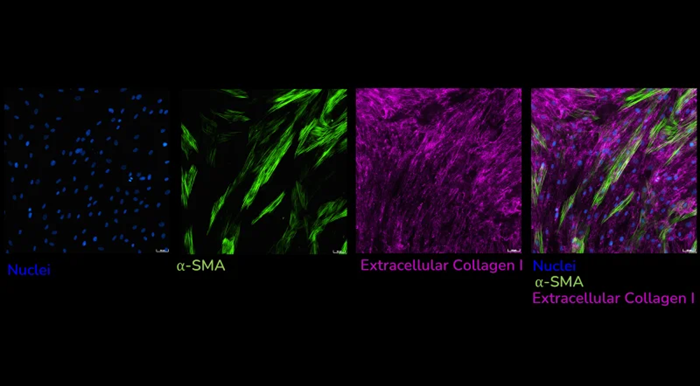

Human lung fibroblasts stimulated with TGF-β1 to detect extracellular collagen I (pink), alpha-smooth muscle actin (α-SMA) (green), and cell nuclei (blue) as a measure of matrix production and fibroblast activation, respectively. Image Credit: Newcells Biotech

Human lung fibroblasts stimulated with TGF-β1 and immunostained to detect extracellular collagen I (pink) and α-SMA (green) as a measure of matrix production and fibroblast activation, respectively. Images captured using ImageXpress Confocal HT.ai imaging system, Scale bar: 50 µM. Image Credit: Newcells Biotech